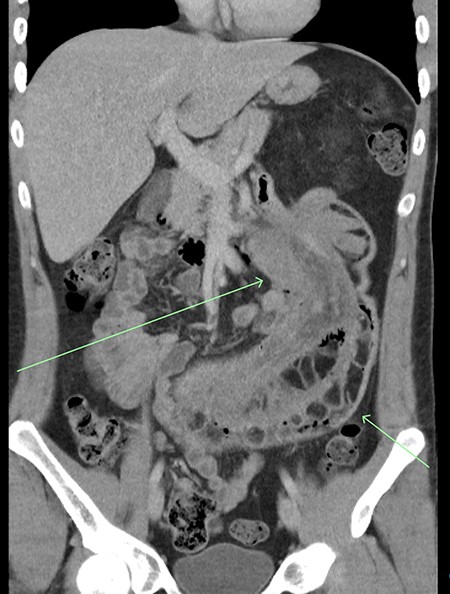

Prior to this presentation, the patient had already had an ultrasound examination and routine biochemistry performed, both unremarkable. Computed tomography (CT) imaging was performed at the time of his second presentation which demonstrated a very large intussusception in the left side of his abdomen with proximal jejuno-jejunal involvement, marked enlargement of the intussuscipiens containing the intussusceptum and an enlarged peri-gastric node measuring 17 × 14 × 14mm at the gastric cardia. There were no imaging features suggestive of ischaemic bowel or intestinal lipomatosis (see Figs 1 and 2).

Coronal view of CT imaging demonstrating a very large intussusception on the left side of the abdomen with proximal jejuno-jejunal involvement. Marked enlargement of the intussuscipiens containing the intussusceptum.